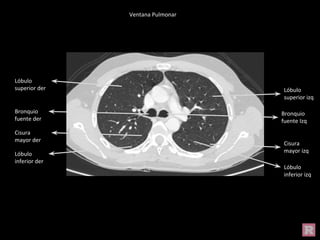

Bronquio

fuente der

fuente Izq

Cisura

mayor izq

Lóbulo

inferior izq

superior izq

superior der

inferior der

mayor der